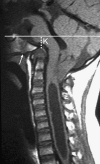

Background: The embryology of the bony craniovertebral junction (CVJ) is reviewed with the purpose of explaining the genesis and unusual configurations of the numerous congenital malformations in this region. Functionally, the bony CVJ can be divided into a central pillar consisting of the basiocciput and dental pivot and a two-tiered ring revolving round the central pivot, comprising the foramen magnum rim and occipital condyles above and the atlantal ring below. Embryologically, the central pillar and the surrounding rings descend from different primordia, and accordingly, developmental anomalies at the CVJ can also be segregated into those affecting the central pillar and those affecting the surrounding rings, respectively.